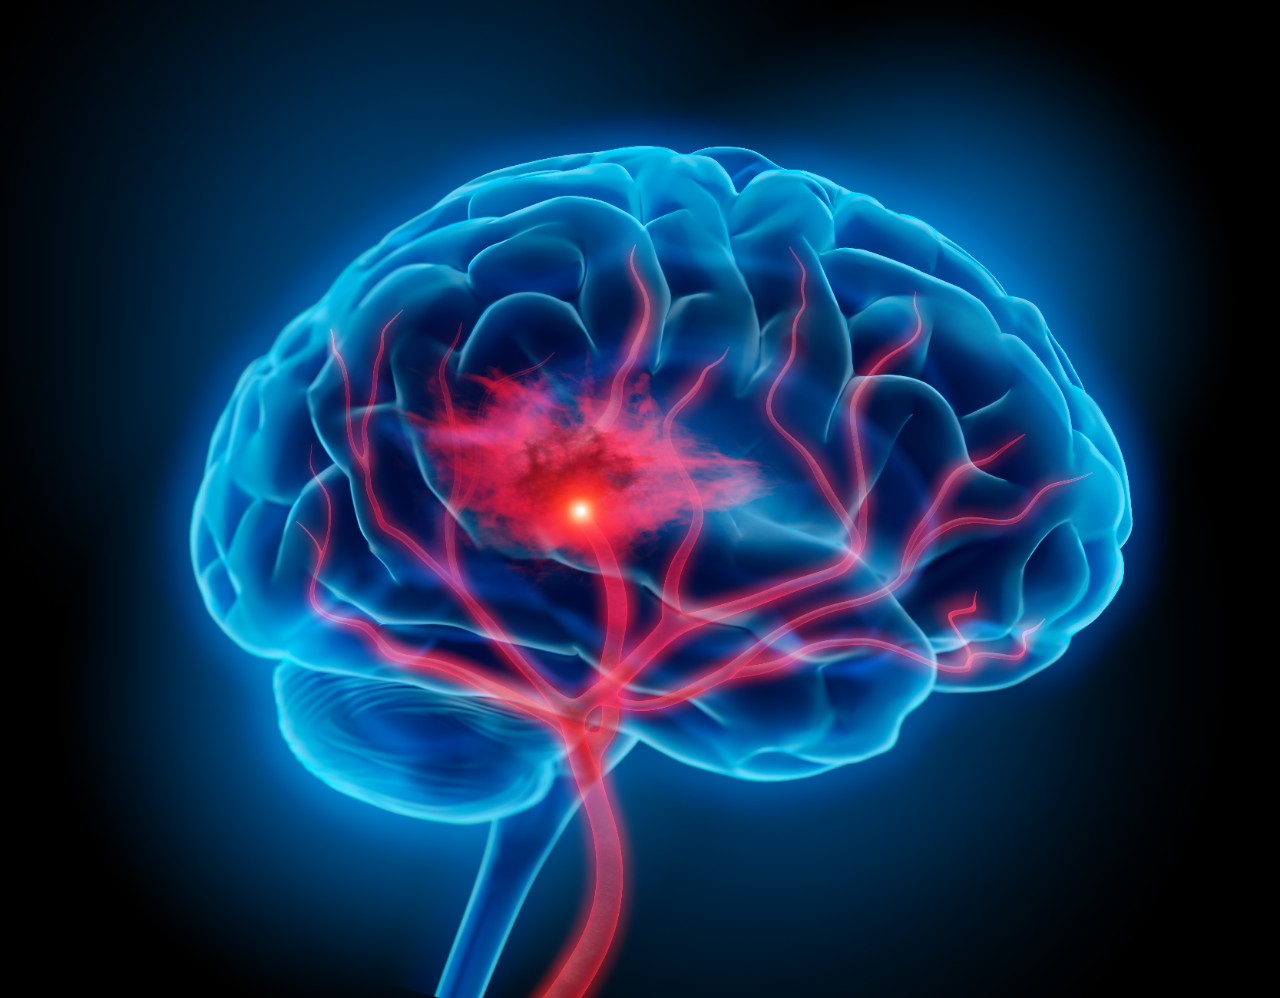

Featured photo at top of illustration of brain with stroke symptoms. Photo/PeterSchreiber.media/iStock.